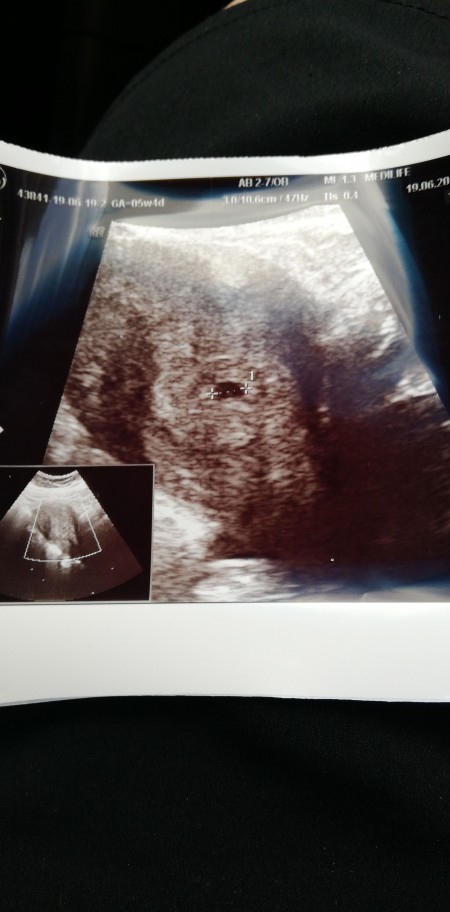

5 1 Gunluk Gebelikte Kese Var Ama Yolk Sac Gorunmedi Normal Mi Kadinlar Kulubu

6 Haftalik 1 5 Aylik Gebelikte Bebegin Ultrason Goruntuleri Yolk Kesesi Kalp Atislari Crl Olcumu Youtube